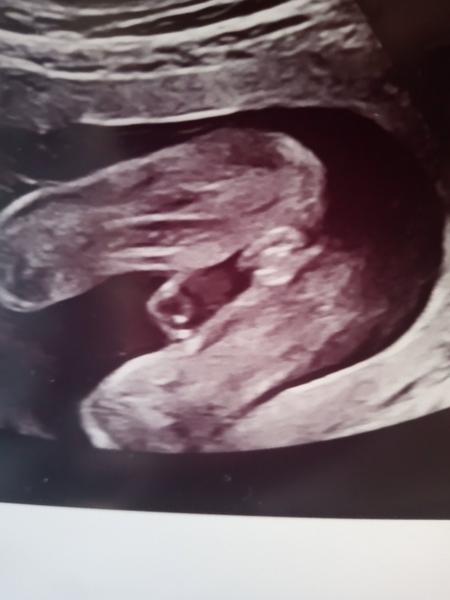

Pohlaví miminka ve 21. týdnu: Poradíte s tipem?

Ahoj, chtěla jsem se zeptat, mám za sebou druhý screening ve 21tt a konečně se nám odhalilo pohlaví (nebudu prozrazovat co mi řekl doktor, abych neovlivnila) ale byla bych ráda, kdyby jste omrkly fotku z utz (je to zespodu pohled mezi nožky) a tiply si, co vidíte. Nám se doteď mimco nechtělo ukázat a pořád se mi výsledku nechce věřit a bojím se něco nakoupit, třeba tu bude někdo znalejsi a uklidní mě :D díky

Tak vám děkuji za uklidnění 🙂 Dr nám taky řekl holku, ale pořád sem tomu nemohla uvěřit :D vůbec netuším jak taková holka na utz má vypadat :D